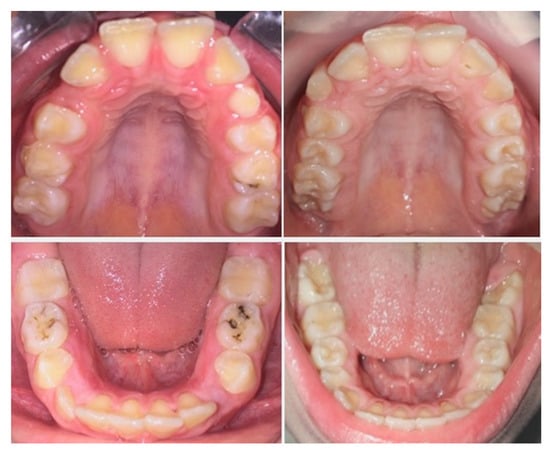

3.1. Outcomes of the Treatment at the One-Year Follow-Up

3.3. Situation of the Treatment after Two Years